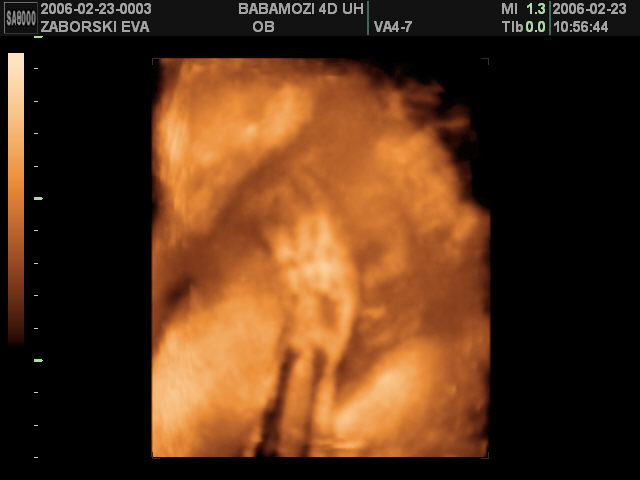

Nicsak! útban vagyok?